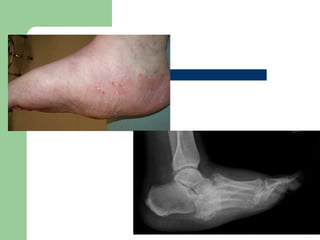

Presentation

 DEPENDS OF DURATION OF DISEASE

 Mild swelling w/o deformity-Moderate

deformity with extreme swelling.

 Signs of inflammation.

 Profound unilateral swelling. WBC and

ESR may

be normal

 Increase in localized

temp

 Erythema,

 Joint effusion.

 75% pt. have pain.

 The deep tendon

reflexes at the knee are

absent in a majority of

patients.